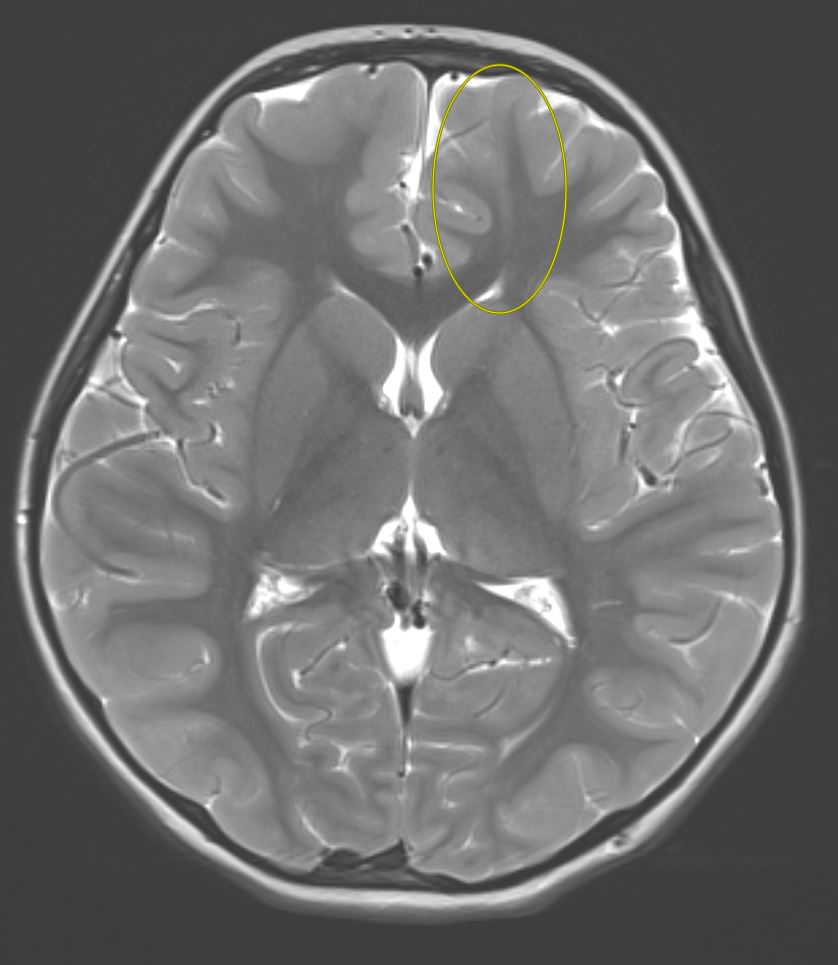

Tip of the day 💡: Spend time optimizing your axial T2 sequence- still the bread and butter sequence for us #radiologists! Here one should pick up the focal cortical dysplasia instantly with the characteristic tail sign. Case closed!